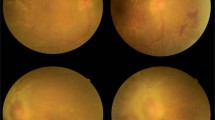

To validate the fundus image grading results by a trained grader (Non-ophthalmologist) and an ophthalmologist grader for detecting diabetic retinopathy (DR) and diabetic macular oedema (DMO) against fundus examination by a retina specialist (gold standard).

A prospective diagnostic accuracy study was conducted using 2002 non-mydriatic colour fundus images from 1001 patients aged ≥40 years. Using the Aravind Diabetic Retinopathy Evaluation Software (ADRES) images were graded by both a trained non-ophthalmologist grader (grader-1) and an ophthalmologist (grader-2). Sensitivity, specificity, positive predictive value and negative predictive value were calculated for grader-1 and grader-2 against the grading results by an independent retina specialist who performed dilated fundus examination for every study participant.

Out of 1001 patients included, 42% were women and the mean ± (SD) age was 55.8 (8.39) years. For moderate or worse DR, the sensitivity and specificity for grading by grader-1 with respect to the gold standard was 66.9% and 91.0% respectively and the same for the ophthalmologist was 83.6% and 80.3% respectively. For referable DMO, grader-1 and grader-2 had a sensitivity of 74.6% and 85.6% respectively and a specificity of 83.7% and 79.8% respectively.

Our results demonstrate good level of accuracy for the fundus image grading performed by a trained non-ophthalmologist which was comparable with the grading by an ophthalmologist. Engaging trained non-ophthalmologists potentially can enhance the efficiency of DR diagnosis using fundus images. Further study with multiple non-ophthalmologist graders is needed to verify the results and strategies to improve agreement for DMO diagnosis are needed.